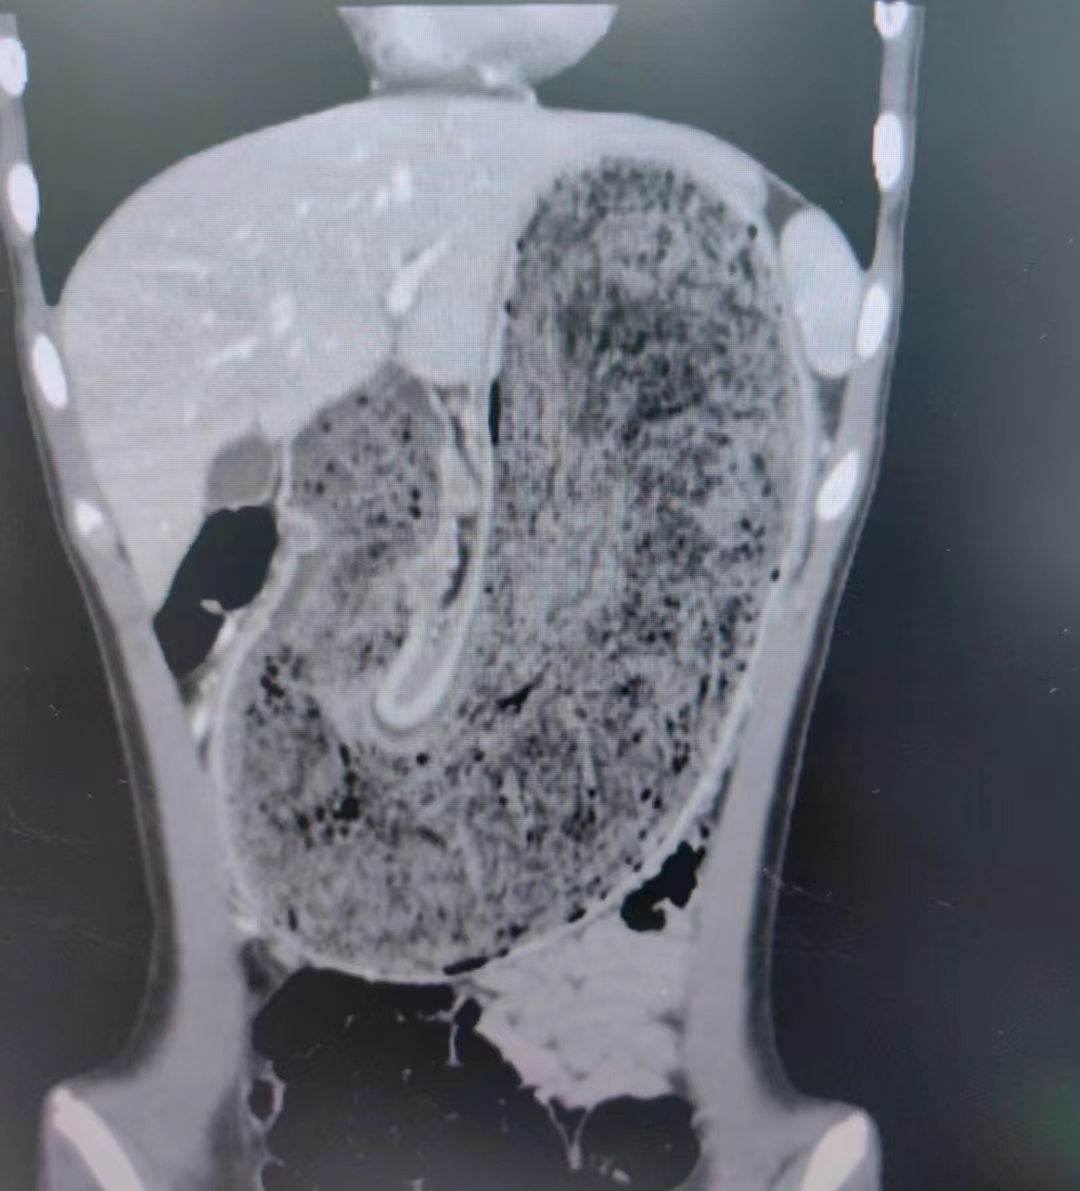

随后,他们将女儿送到东莞市妇幼保健院。内科医生张铭承接诊后对欢欢进行检查,结果惊讶地发现,欢欢的胃腔和肠管里有大块的毛絮状结石,几乎占据整个胃部——这就是腹痛的根源。

考虑到结石太大无法自行排出,并且由于时间太长,毛发团坚如磐石,胃镜下取出同样困难重重,东莞市妇幼保健院多学科专家会商,为欢欢制定了快速清除巨大毛发胃石症的腹腔镜手术。

东莞市妇幼保健院小儿外科主任伍岗泉主刀,他带领团队耗时近60分钟,将长38厘米×宽15厘米×厚10厘米的毛发结石从欢欢胃部成功取出。欢欢的毛发胃石巨大,严重影响进食和生长发育,通过手术,欢欢腹痛消除,恢复良好。